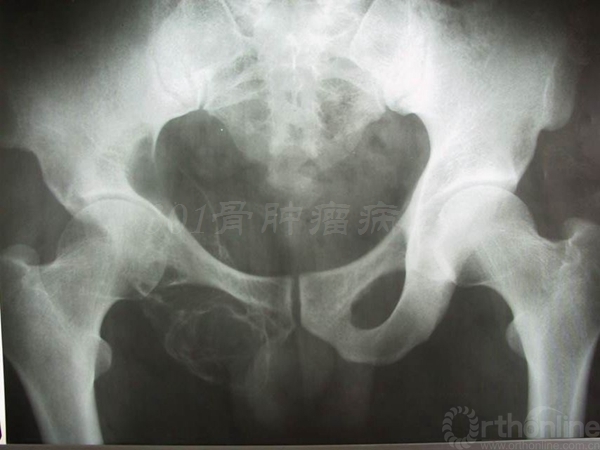

患者女性,术前X片提示:左侧骨盆Ⅱ+Ⅲ区溶骨性改变,诊断考虑骨巨细胞瘤合并动脉瘤样骨囊肿。血管栓塞后行骨盆Ⅱ+Ⅲ区切除,股骨头旷置术。术后病理报告是骨巨细胞瘤恶变,故行化疗6个月。术后13年随访,患者有跛行,但行走自如。

术后13年X线片